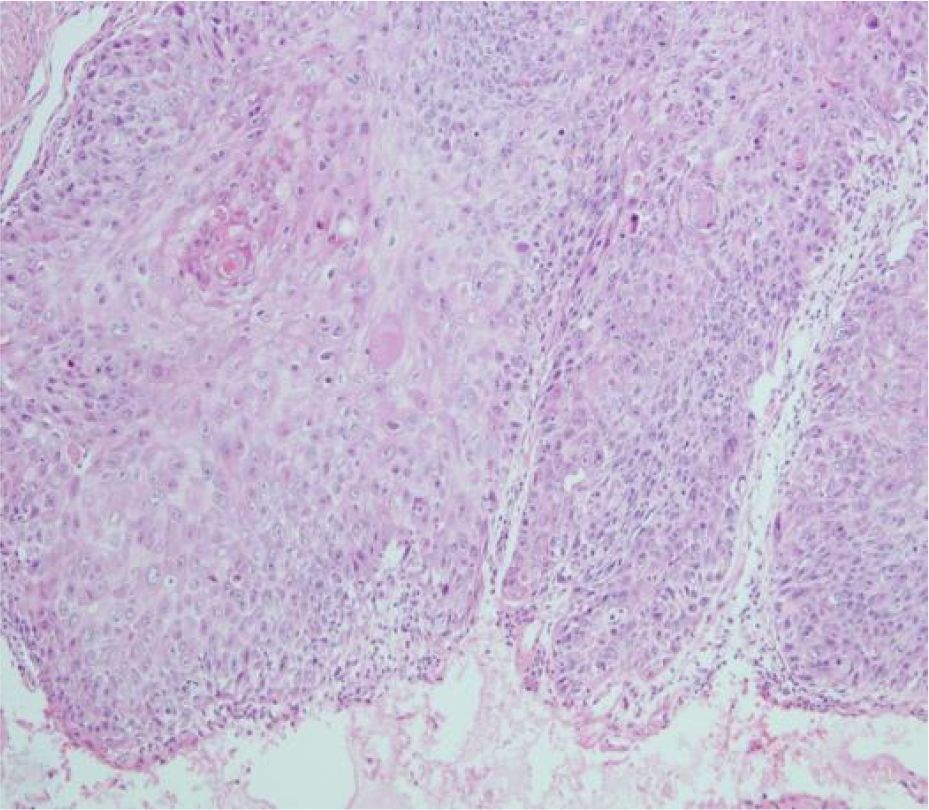

Figure 3

Microscopic image of tissue stained in shades of pink and purple, showing densely packed cells with prominently visible nuclei. The irregular shapes and sizes suggest a biological or medical context.

Figure 3. Pathological section.

A 51-year-old middle-aged man inadvertently noticed a soybean-sized swelling on the perianal skin, without obvious symptoms such as itching, pain, or bleeding and discharge. Three months later, the swelling gradually increased in size, accompanied by itching and discharge (Figure 1). A pathological biopsy revealed “perianal” Bowen’s disease (Figures 2, 3), with suspected focal infiltration. After consultation with a surgical team, it was determined that the patient’s perianal tumor had grown significantly, involving the scrotum and perineum, with poor mobility, making radical resection impossible. Following departmental discussion, the patient was treated with tislelizumab and capecitabine chemotherapy, along with topical application of fluorouracil ointment on the tumor. After two cycles of treatment, the tumor was significantly reduced, and the third cycle of treatment was continued (Figure 4). However, the patient did not proceed with the fourth cycle of treatment due to personal reasons. Subsequent follow-ups have shown that the patient has survived for two years since then.